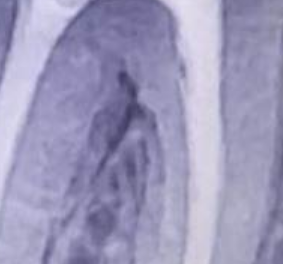

Aleksandr21321 Опубликовано 27 декабря, 2023 Автор Поделиться Опубликовано 27 декабря, 2023 11 часов назад, Notherbrick сказал: Если трещина подтвердится- удаление. Кариес найдете, если смотреть вертикально вверх от вашей отметки. Между пломбой и корнем зуба горизонтальная темная полоса. Вот КТ, который делал пару месяцев назад сразу же после удаления нерва Ссылка на комментарий

Notherbrick Опубликовано 28 декабря, 2023 Поделиться Опубликовано 28 декабря, 2023 Зуб депульпирован, поэтому кариес не при чем. И второй снимок это оптг. Кт это трехмерная реконструкция. Но судя по панорамному снимку беспокоить вполне может и впередистоящий 46 зуб. Ссылка на комментарий